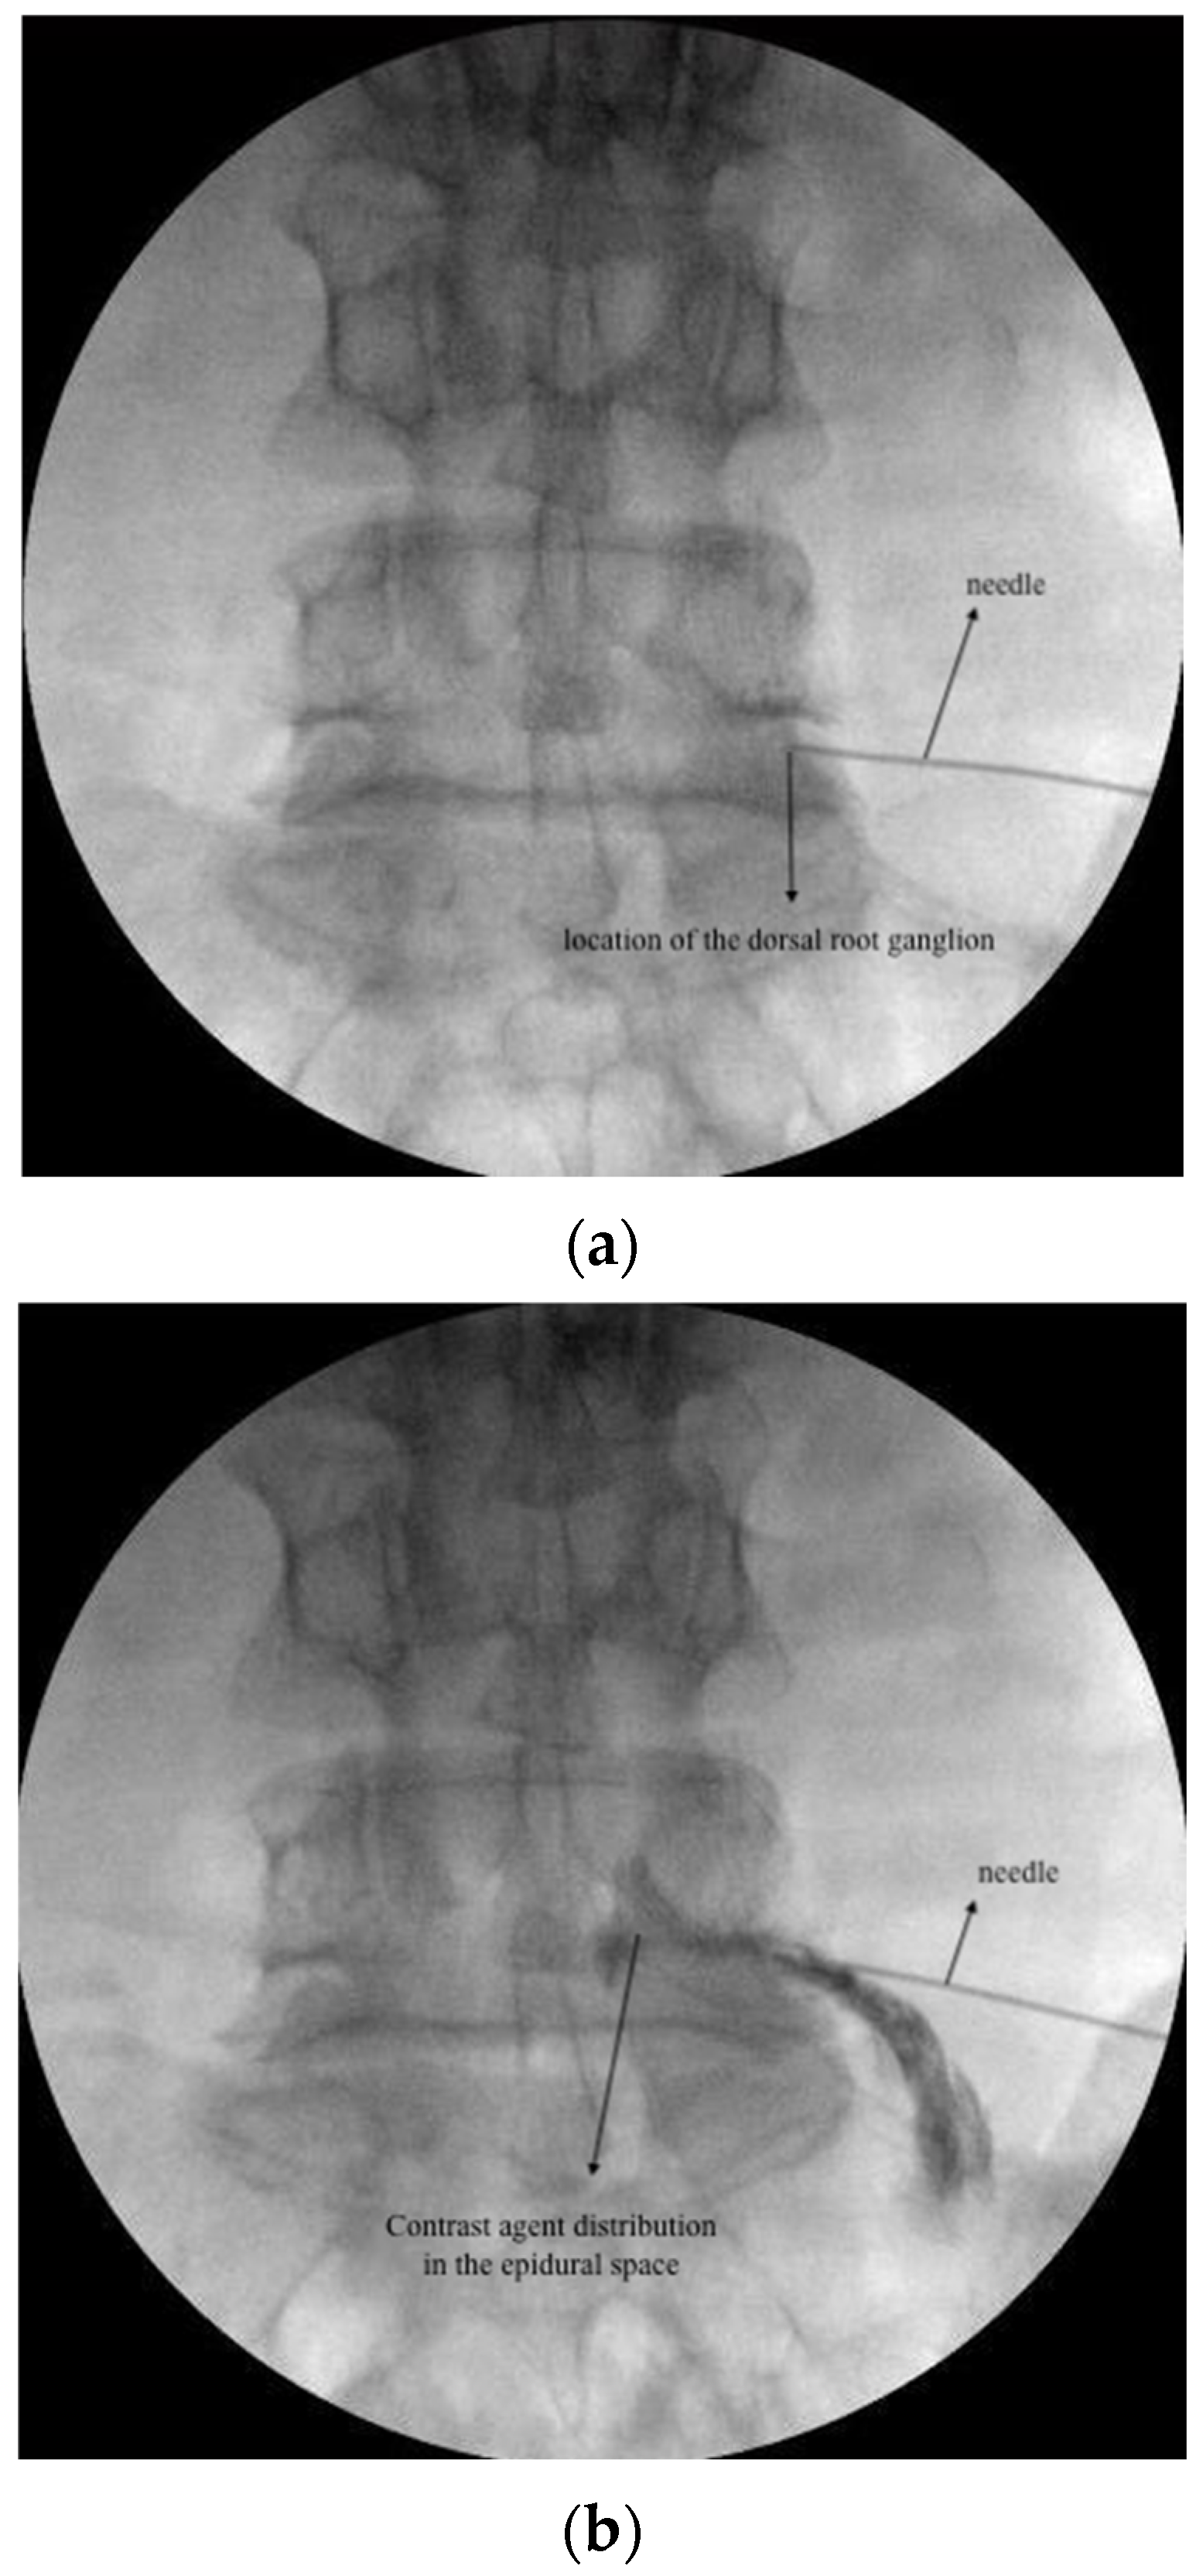

For TESI, the needle tip was retracted 2–3 mm to realign in the safe triangle following DRG PRF. Epidural spread was verified using contrast medium (Omnipaque 300, GE Healthcare, Dublin, Ireland). A total of 5 mL (4 mg/1 mL dexamethasone and 4 mL 0.9% NaCl) was injected at each target level (Figure 1a,b).

Figure 1.

(a): DRG PRF fluoroscopic image; (b): TESI fluoroscopic image; (c) CESI fluoroscopic image.